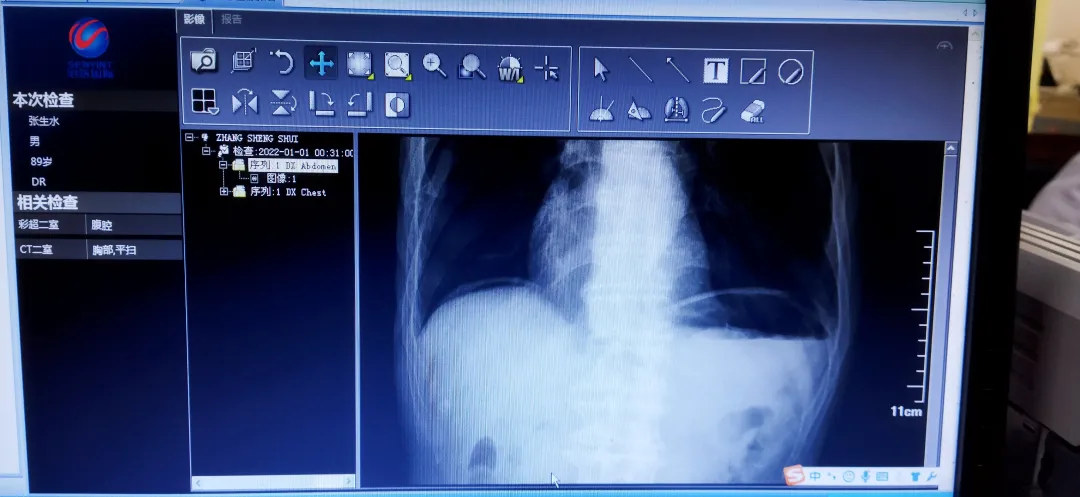

张爷爷术前检查及术后查房情况

1、原来张爷爷是隆回境内一位参加过抗美援朝的老兵, 2021年12月31日下午5时许,居住在老家鸭田镇坪头村的张爷爷突然腹痛如绞伴恶心、呕吐,当时正巧回家看望父亲的患者女儿不敢大意,急忙送张爷爷至当地金石桥医院看病,急诊CT提示老人家“消化道穿孔”,遂由120急送患者至隆回县人民医院胃肠外科,当晚便进行了微创手术——“腹腔镜下十二指肠穿孔修补术”。

2021年12月31日半夜23:22分入院的张爷爷,成功做完急诊手术时已经是2022年1月1日凌晨1点多!据张爷爷后来的回忆,整个治疗过程中除了可以忽略不计的腹部轻微不适外,几乎没有明显的疼痛或者痛苦的感受,当今医院医疗、手术水平的进步让张爷爷赞叹不已,老人家和家属一致夸奖医院医护团队:技术过硬、医术高超、服务态度极佳,不愧是隆回县城的三级医院。